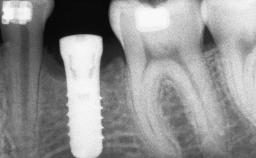

Ridge Preservation and Implant Placement for a Fixed Dental Prosthesis After a Car Accident

It is well known to clinicians that any removal of teeth will, over time, cause the dimensions of the alveolar ridge to be reduced by resorption of the bundle bone and by changes related to external modeling. This development is particularly evident in the crestal region with its thin buccal bone that consists of bundle bone almost entirely. The facial bone will rapidly resorb as blood supply from the periodontal ligament gets disrupted (Araújo and Lindhe 2005). There is no reason why traumatic tooth loss should not have the same consequences. It takes more than achieving implant osseointegration for a treatment outcome to be considered successful. No deficiency of bone or soft tissue is acceptable when an ideal esthetic outcome is the goal. Several articles (Sanz and coworkers 2011; Vignoletti and coworkers 2011) have reported on techniques of improving the alveolar ridge for implant treatment, notably focusing on protecting tissues from resorption.